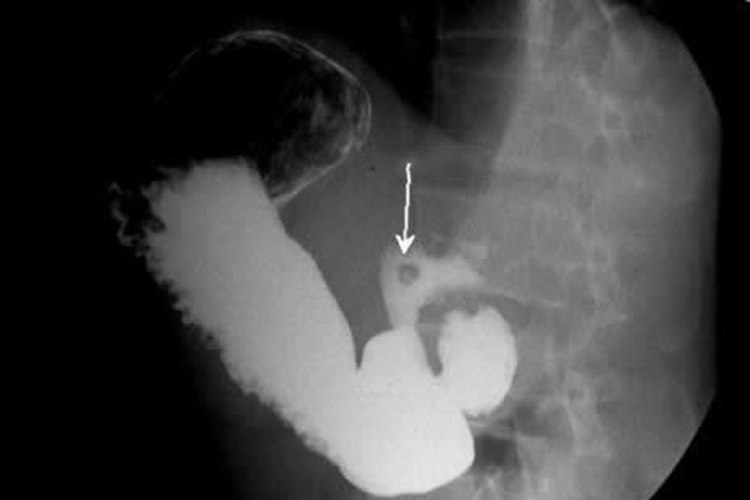

胃肠道肿瘤:局部充盈缺损,形状不规则,管腔狭窄,管壁狭窄,龛影,边缘不整,位于管腔轮廓内,黏膜皱襞破坏,中断,消失。